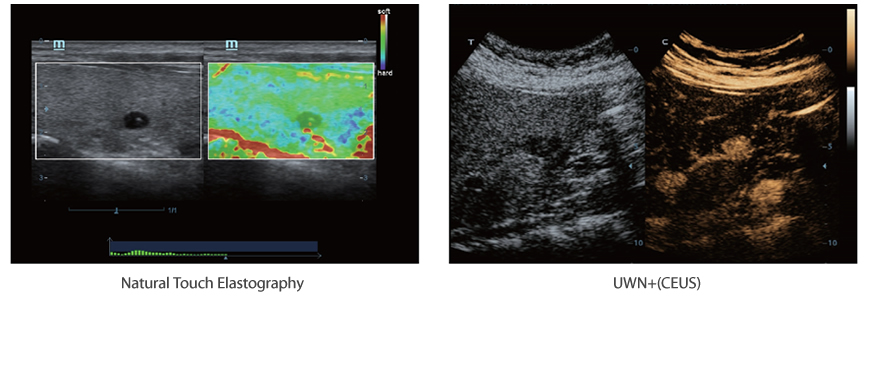

Combining with Instromedix India unique 3T technology (Triple-matching layers, Total-cut design, Thermal control), the optimized convex, phased array and volume transducers provide a wider full range application coverage, resulting in an optimum scanning solution in ABD, Cardiology, OB/GYN and more.